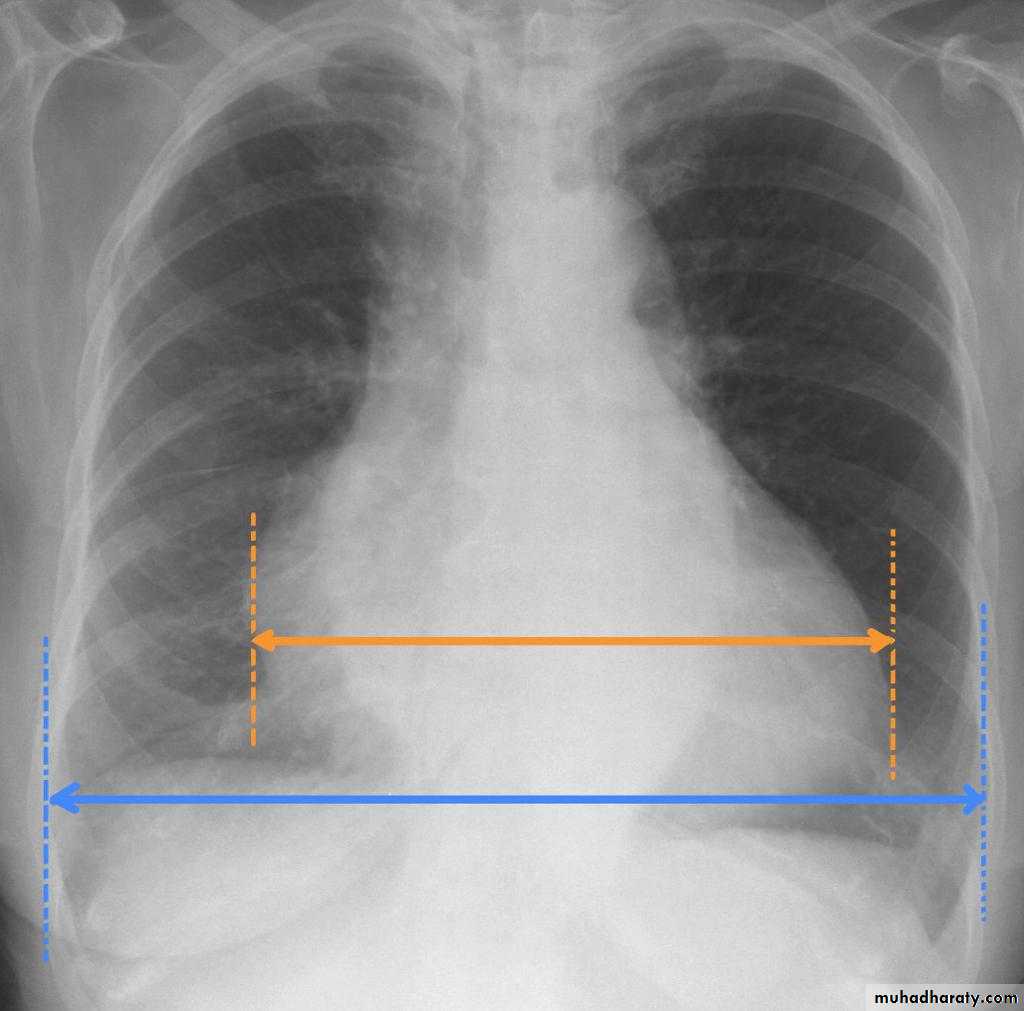

Who to asses cardiac size

Retrosternal Goiter

13.who to asses cardiac size

14.cardiac border in AP view